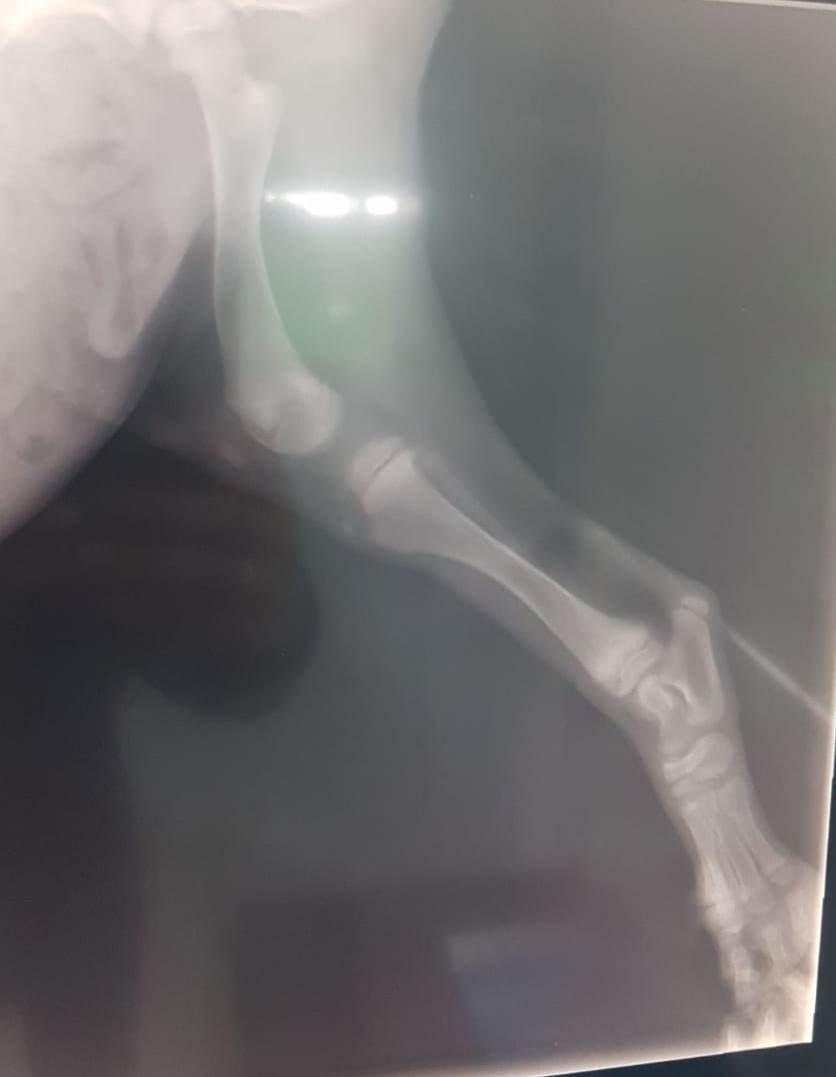

Es habitual en cachorros de razas grandes, que tienen un crecimiento tan súbito, que se produzcan algunas incidencias en sus patas. Hace algunos días observamos que Denni tenía algún problemilla en una de sus patas traseras y, para evitar males mayores, lo llevamos a hacer radiografías. El veterinario nos ha indicado que con la colocación de una simple férula y como aún tiene que crecer tanto, probablemente se solucione el problema sin necesidad de intervención ni medicación.

Os dejamos las fotografías de las radiografías y algunas fotos del peque en el veterinario.